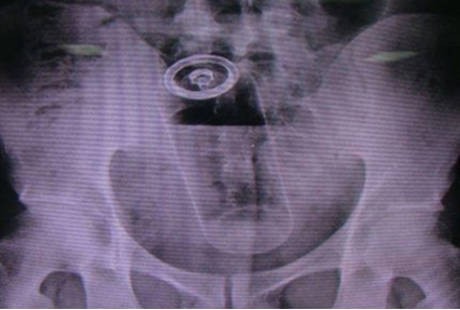

Pria muda ini mendatangi Riyadh Care Hospital di Arab Saudi dengan keluhan nyeri di perut bagian bawah. Selepas menjalani scan, ia dokter menemukan ada sebuah obyek yang tersangkut di dalam ususnya. Di akhir pemeriksaan, barulah si pasien mengaku ia sendiri yang memasukkan benda tersebut ke dalam anusnya, meski tak mengatakan alasan di balik itu.

Kaleng deodoran itu pun bisa diambil secara manual karena letaknya dekat dengan anus. Tindakan ini dilakukan dengan pasien diberi anestesi terlebih dahulu. Keesokan harinya, ia sudah diperbolehkan pulang.